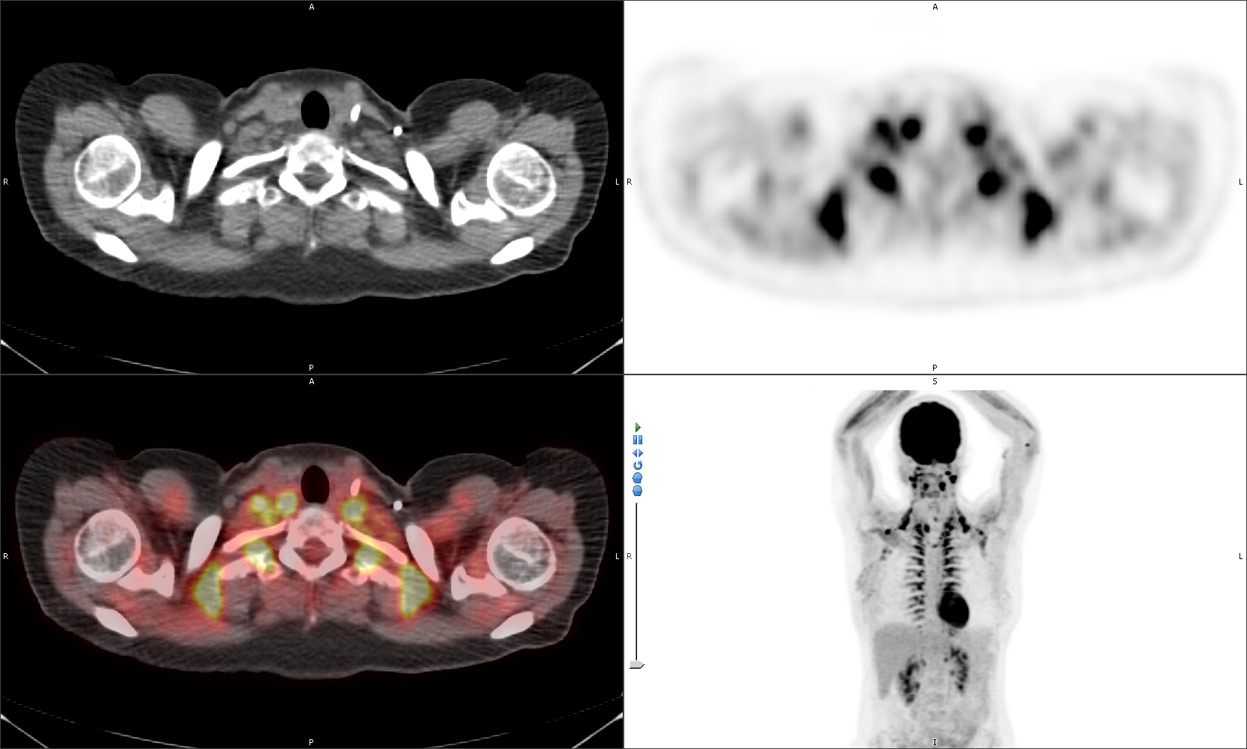

Fused axial FDG PET-CT (B), PET axial (C), CT axial (D) and MIP PET (E) images demonstrate intensely FDG avid lymph node in the right axilla. Infiltration of FDG at the injection site in right antecubital fossa results in lymphoscintigraphy with FDG migrating to the regional nodal basin via the lymphatic ducts. |

| Fused axial FDG PET-CT (B), PET axial (C), CT axial (D) and MIP PET (E) images, demonstrate intensely FDG avid lymph node in the right axilla. Infiltration of FDG at the injection site in right antecubital fossa results in lymphoscintigraphy with FDG migrating to the regional nodal basin via the lymphatic ducts. |